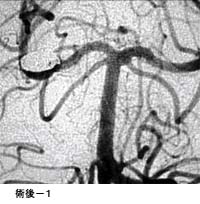

(1)破裂脳動脈瘤に対するGDC(コイル)塞栓術

*術後 コイルにより動脈瘤が写らなくなりました。